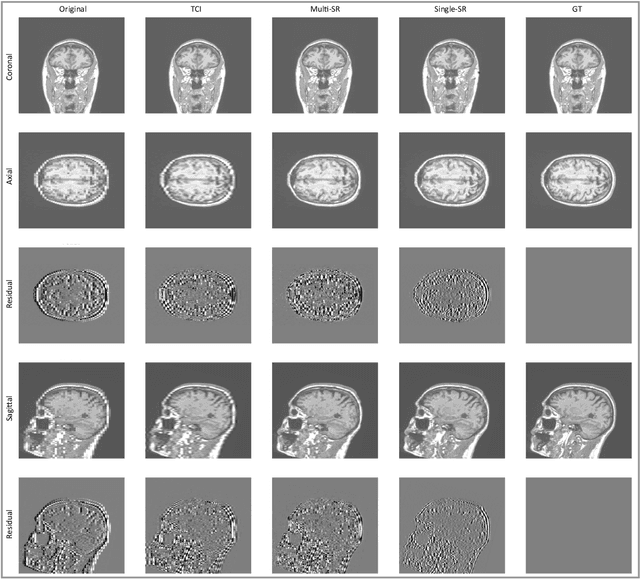

Abstract:There is a growing demand for high-resolution (HR) medical images in both the clinical and research applications. Image quality is inevitably traded off with the acquisition time for better patient comfort, lower examination costs, dose, and fewer motion-induced artifacts. For many image-based tasks, increasing the apparent resolution in the perpendicular plane to produce multi-planar reformats or 3D images is commonly used. Single image super-resolution (SR) is a promising technique to provide HR images based on unsupervised learning to increase resolution of a 2D image, but there are few reports on 3D SR. Further, perceptual loss is proposed in the literature to better capture the textual details and edges than using pixel-wise loss functions, by comparing the semantic distances in the high-dimensional feature space of a pre-trained 2D network (e.g., VGG). However, it is not clear how one should generalize it to 3D medical images, and the attendant implications are still unclear. In this paper, we propose a framework called SOUP-GAN: Super-resolution Optimized Using Perceptual-tuned Generative Adversarial Network (GAN), in order to produce thinner slice (e.g., high resolution in the 'Z' plane) medical images with anti-aliasing and deblurring. The proposed method outperforms other conventional resolution-enhancement methods and previous SR work on medical images upon both qualitative and quantitative comparisons. Specifically, we examine the model in terms of its generalization for various SR ratios and imaging modalities. By addressing those limitations, our model shows promise as a novel 3D SR interpolation technique, providing potential applications in both clinical and research settings.